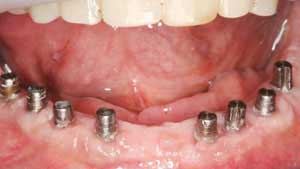

Kaybedilen dişlerin yerine tedavi amacı ile yerleştirilen ve organizma için herhangi bir yan etkisi olmayan, kemik dokusu ile birleşimini tamamladıktan sonra da doğal bir diş gibi iş görebilen, titanyumdan yapılmış; plak, vida ve çivilere implant denir.

Kök, silindir ya da vida şeklinde biçimlerindirilen titanyum, özel birtakım işlemlerden geçirildikten (özel tasarım asitleme, lazerle pürüzlendirme vb.) sonra dental implant olarak kullanıma hazır hale gelmektedir. Bu işlemler implantın kalitesini belirler.